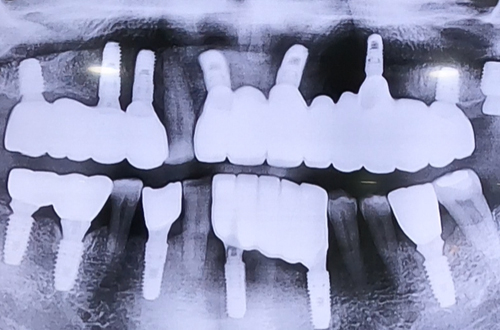

AFTER

치료 유형 전체임플란트

아랫니 상태는 양호하였으므로 상태가 많이 안 좋은 윗니의

전체 임플란트 치료를 진행하게 되셨는데요.

검사를 해 보니 오른쪽 위 송곳니는 단단하게 상태가 좋았으므로

해당 송곳니를 남겨두고 나머지 전체 임플란트를 하기로 결정했습니다.

임플란트 식립 후 4개월 간 굳는 기간을 기다리고 예쁘게 보철까지 완성해 드렸습니다.